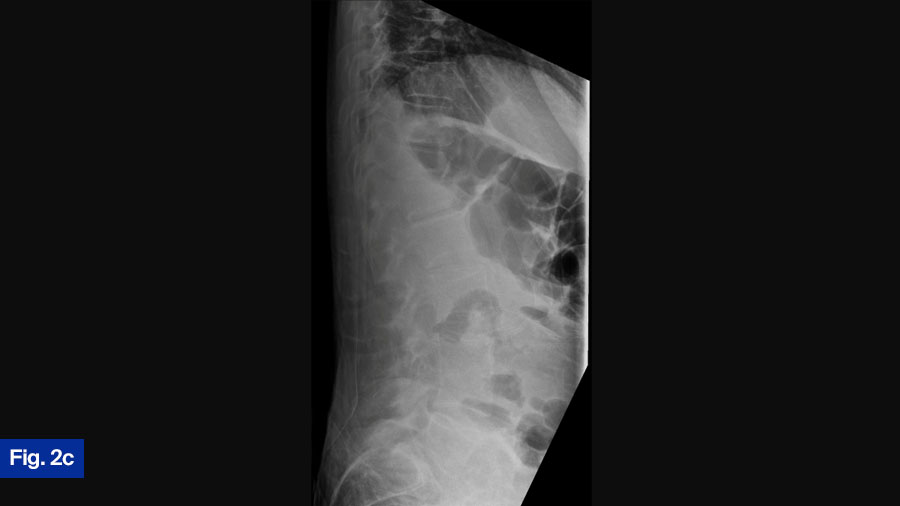

- Upright radiographs: Further evaluated spinal stability (Figure 2c).

This case is certainly controversial. At my institution, when such a case is presented at rounds, the room is divided regarding best treatment (initial medical treatment versus initial surgical treatment). Interesting and lively debates occur. This patient presents with a new diagnosis of discitis/osteomyelitis with some bony destruction and epidural abscess. He is neurologically intact and upright radiograph show the segment to be stable. Given this, I would admit the patient and attempt initial medical management. I would monitor response to treatment clinically as well as via laboratory inflammatory markers. Often, in the context of infection that receives adequate medical treatment, we see fusion of the segment. However, this patient will need to be monitored closely once discharged from the hospital with regular clinical assessments with upright radiographs as well as close monitoring by the infectious disease team. It is still possible that this patient requires surgical intervention. Given the growing international academic interest in this disease and the possible growing evidence that initial surgical intervention is best, it is possible that my approach to these types of cases will change as we reach consensus on best treatment.